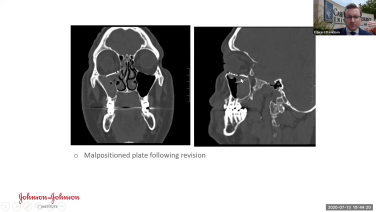

Midface Trauma Fractures: Challenges in VSP & Additive Technologies with Nagi Demian, MD